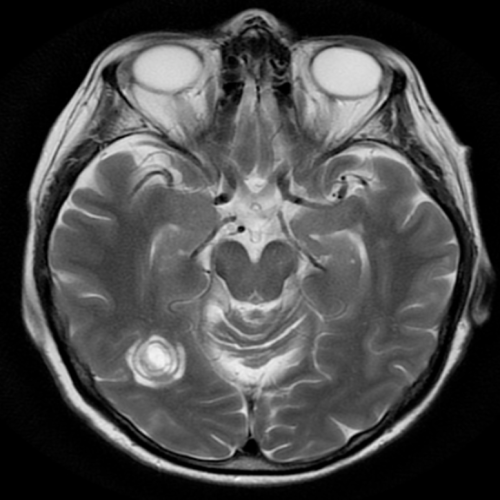

Paziente uomo con progressivi disturbi visivi. La RM encefalo mostra questa lesione:

Il reperto sarebbe più compatibile con la diagnosi di:

- Sindrome di Balò

- Sindrome di Devic

- SLA

- Pseudotumor cerebri

- Meningite tubercolare

La sindrome di Balò (Risposta esatta: A) è una forma rara di leucoencefalopatia caratterizzata da lesioni concentriche, che si presentano come anelli alternati di alta e bassa intensità in RM. Queste lesioni tipicamente colpiscono i giri longitudinali e periventricolari del cervello, e il loro aspetto è descritto come “anelli di cipolla”. L’aspetto concentrico delle lesioni è uno dei segni distintivi della sindrome di Balò, che può essere un fenomeno acuto o subacuto e spesso è associato a disturbi neurologici progressivi.